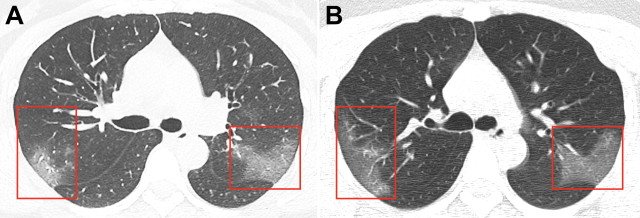

Изображенията са получени в резултат на компютърна томография на 33-годишна жена, хоспитализирана в китайския град Ланджоу с температура от 39 градуса. Тя е работила в Ухан.

Първата снимка показва замъгляване, създавайки "ефект на матирано стъкло" на дроба. Това е в резултат на влиянието на коронавируса в първите дни на заболяването.

На втората снимка са показани белите дробове на жената само три дни по-късно с огромни поражения.